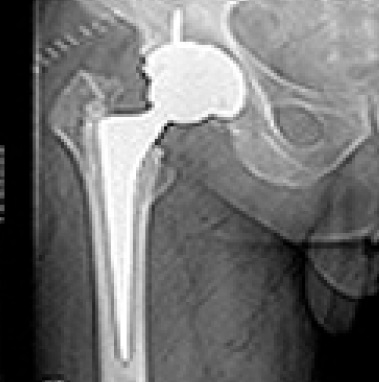

Total Hip Replacement

Lorem ipsum dolor sit amet consectetur. Sed nulla nulla ligula tincidunt ac euismod mauris ultrices facilisis egestas duis.